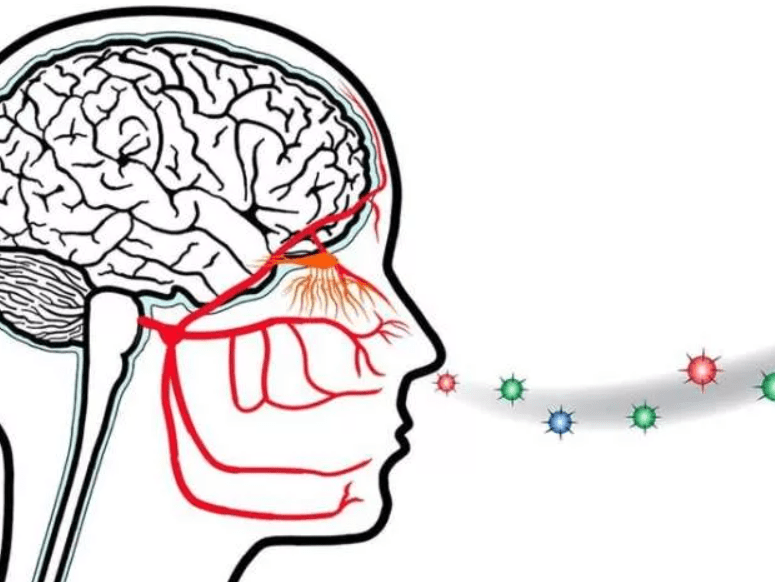

- вы отметили, что во время болезни у вас пропадало обоняние, привычный вкус еды тоже менялся;